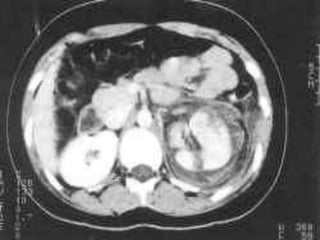

Grading system of renal trauma

Grade

I

Grade II

Grade Grade IV

Grade V

Radiological grading

1: Minor injury

contusion, intrarenal or subcapsularhematoma, minor

laceration with limited perirenal hematoma without extension into

collecting system or medulla,subsegmentalcortical infarct

2: Major

laceration extending from cortex to medulla/collecting system

with/without extravasations, segmental infarct

3: Catastrophic

Multiple lacerations, pedicular injury

4: PUJ avulsion